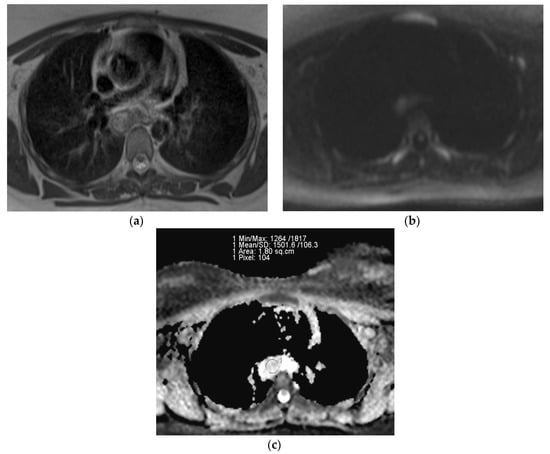

The representative T2-weighted images, DWI, and ADC maps of the malignant and benign lymph nodes are shown in Figure 2 and Figure 3 respectively.

Figure 3.

(a) T2-weighted axial MRI of 26-year-old female shows T2 heterogeneity in lymph nodes at subcarinal location (station 7); (b) Diffusion-weighted axial MRI shows mild central diffusion restriction; (c) Systemgenerated ADC map of corresponding lymph node shows ADC mean value of 1.501 × 10−3 mm2/s. The final pathological diagnosis was tuberculosis.